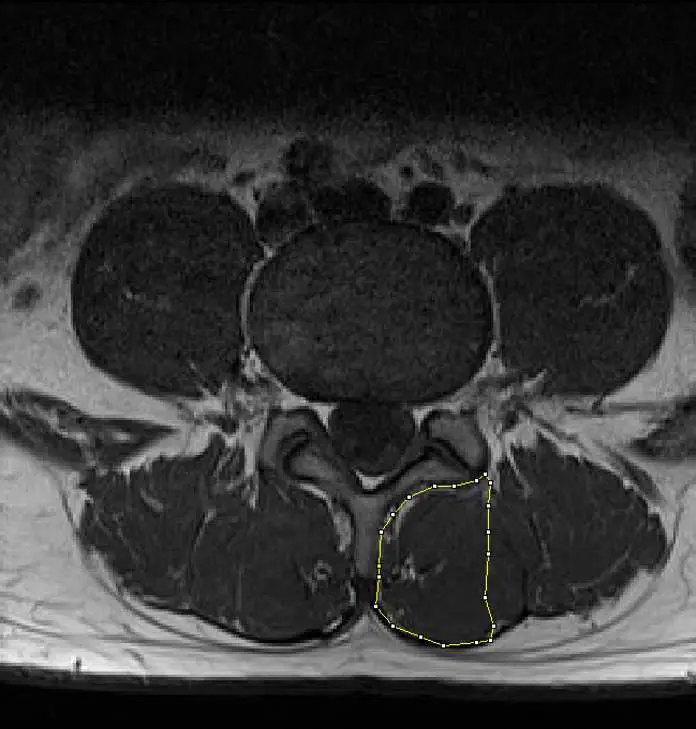

此圖為一名下背痛患者之腰椎軸面( axial plane )T1 加權( T1-weighted )核磁共振影像,所圈選的組織顯示出有脂肪的浸潤( fatty infiltration ),應建議患者接受下列何種治療?

本題圖片為腰椎軸面(axial plane)T1 加權(T1-weighted, T1W)核磁共振影像。

- 影像平面:軸面(橫斷面),顯示腰椎某一節段的截面,可見椎體(vertebral body)前方、椎弓(vertebral arch)、以及兩側的椎旁肌群

- 正常肌肉訊號:T1 加權影像中,健康骨骼肌呈均勻的中等灰色訊號(intermediate signal intensity);脂肪在 T1 中呈高訊號(hyperintense),即明亮白色

- 圈選組織(黃色輪廓標示):影像左側(解剖學右側)的椎旁肌群以黃色輪廓標記,該區域肌肉內可見明顯的高訊號亮白區域混雜於肌肉實質中,代表脂肪組織浸潤取代了正常肌肉纖維,此為脂肪浸潤(fatty infiltration)的典型 T1 影像表現

- 受影響肌肉:依據軸面位

腰椎旁肌(paraspinal muscles)脂肪浸潤(fatty infiltration)的 MRI 影像判讀,以及針對核心肌群萎縮的物理治療介入選擇。脂肪浸潤是腰椎多裂肌(multifidus muscle)功能退化的影像學標誌,對應的最佳治療為脊椎穩定運動(spinal stabilization exercise)以重建核心肌群的神經肌肉控制與肌力。